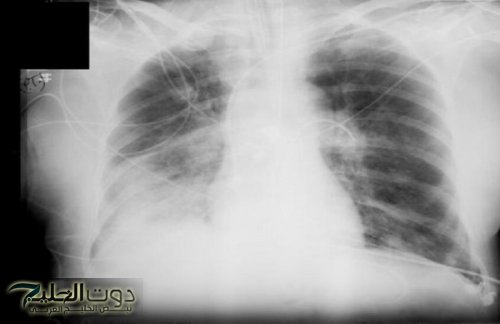

وتقول: "الأشعة السينية هي إشعاع كهرومغناطيسي، مثل الأشعة فوق البنفسجية والضوء والحرارة. صحيح قد تلحق جرعاتها العالية الضرر بالخلايا، كالذي تسببه حروق الشمس. وأن الاستلقاء تحت أشعة الشمس على الشاطئ دون حماية أخطر بكثير من تصوير بالأشعة السينية للصدر مرة واحدة سنويا".